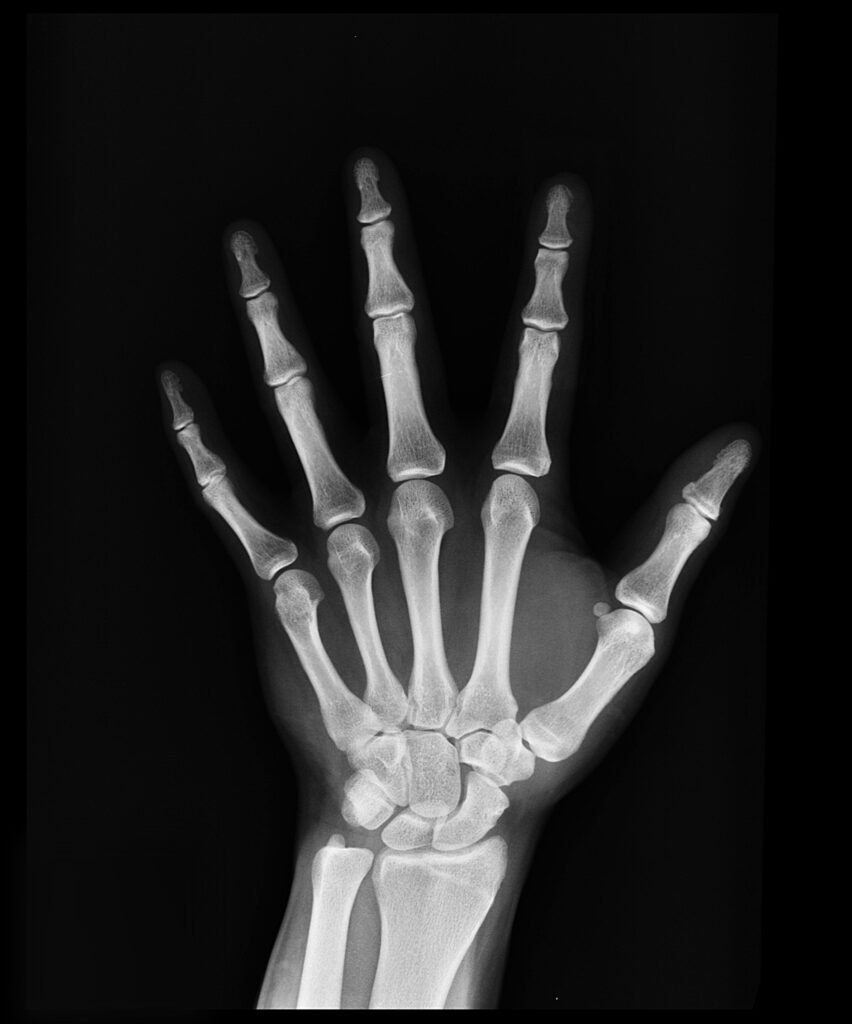

Die Röntgenbildgebung ist in der medizinischen Diagnostik und Materialforschung unverzichtbar. Um ein Bild zu erzeugen, wandelt ein Detektor die Röntgenstrahlen, die das Objekt durchdrungen haben, von einem Detektor in elektrische Signale um. Je empfindlicher diese Detektoren reagieren, desto niedriger kann die Strahlenbelastung für die Probe ausfallen. Insbesondere in medizinischen Anwendungen wäre dies sehr günstig.

Getestet wurden die Pellets als so genannte Flachdetektoren für Röntgenstrahlung in der Gruppe von Dr. Felix Lang an der Universität Potsdam. „Die Ergebnisse zeigen, dass sie selbst über lange Zeiträume besser funktionieren als derzeit handelsübliche Detektoren“, sagt Starkholm. „Tatsächlich weisen sie eine um bis zu zwei Größenordnungen höhere Empfindlichkeit auf als handelsübliche Materialien wie amorphes Selen oder CdZnTe – und können fast 50-mal niedrigere Röntgendosen detektieren“, sagt Starkholm.

„Diese Ergebnisse zeigen, wie spannend es sein kann, die Forschung an Hybridmaterialien am HZB über die Photovoltaik hinaus auszuweiten, sowohl innerhalb als auch außerhalb des Perowskitbereichs. Unsere Studie belegt, dass diese völlig neuen Materialien auf Wismutbasis hervorragende Kandidaten für die Röntgendetektion sind. Mit empfindlicheren Röntgendetektoren könnte die Strahlenbelastung bei der Röntgenbildgebung deutlich reduziert werden“, sagt Olena Maslyanchuk.